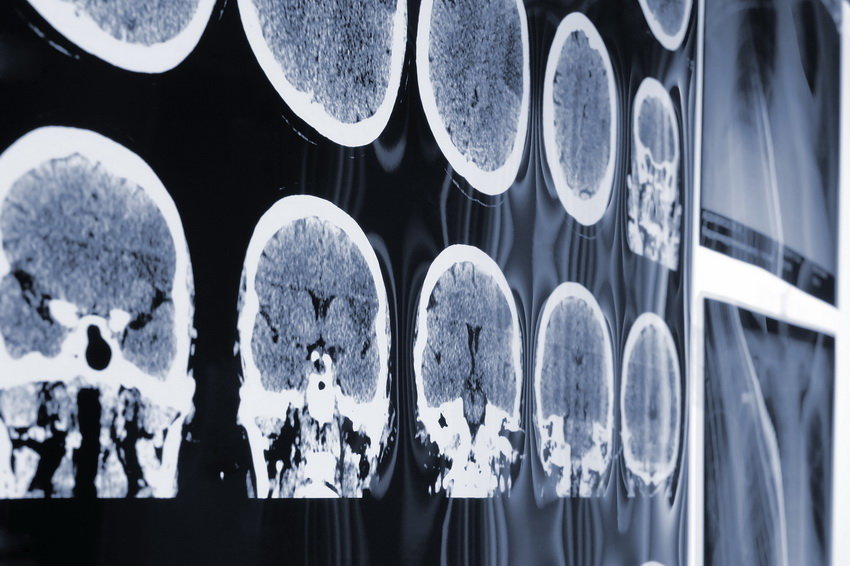

Ученые впервые выявили область в мозге, ответственную за "эффект плацебо" в ослаблении боли, когда таблетка-пустышка действительно облегчает страдания пациента, сообщается на сайте Северо-Западного университета в Чикаго (США). Сделанное открытие поможет разработать методы персонализированной медицины для людей с хронической болью и более точно подбирать лекарства для конкретного человека в зависимости от того, как их мозг реагирует на препарат. В исследовании приняли участие несколько десятков человек, половина из которых получала настоящие обезболивающие, а вторая половина - плацебо. С помощью функциональной магнитно-резонансной томографии (ФМРТ) ученые смогли отследить, как именно мозг реагирует на прием препаратов. В итоге в пределах средней лобной извилины была обнаружена область мозга, в которой нейроны отвечали на прием плацебо, в ходе повторного испытания точность результатов совпала на 95 процентов. - Новая технология позволит врачам увидеть, какая часть мозга активизируется во время боли индивидуума и выбрать конкретный препарат для воздействия на выбранное место, - отметил один из авторов исследования, профессор физиологии Ваня Апкарян. |